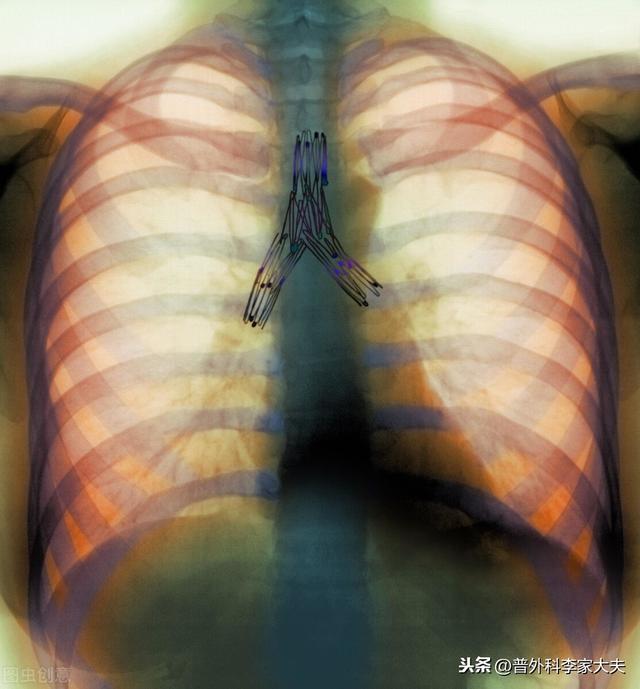

chirurgie pulmonaire par thoracoscopie

opération radicale du cancer du poumon